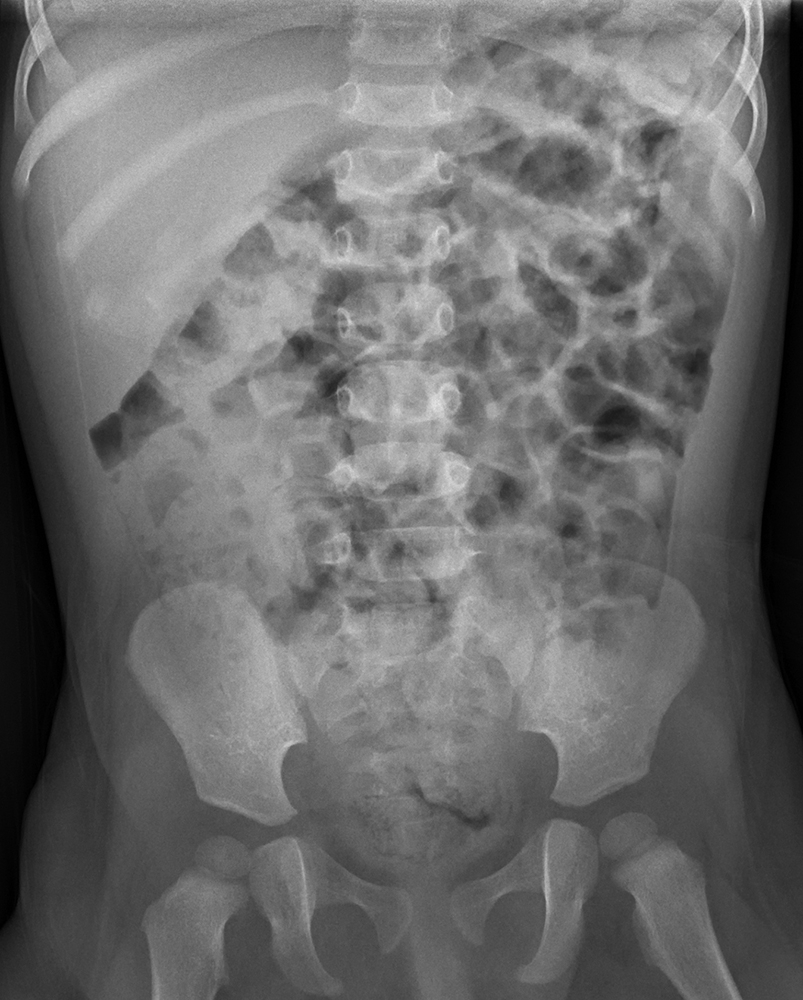

Non Obstructive Bowel Gas Pattern Treatment Www lx iriss uk